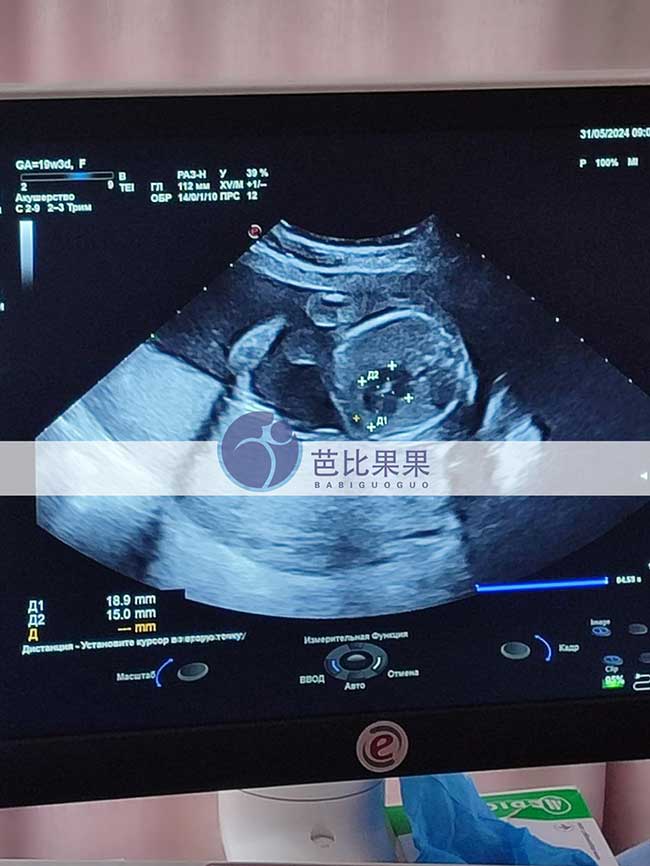

山东H夫妇在格鲁吉亚自卵助孕匹配的试管妈妈做19周B超

山东H夫妇在格鲁吉亚自卵试管助孕匹配的乌克兰试管妈妈来医院做19周B超,胎儿长势很好。